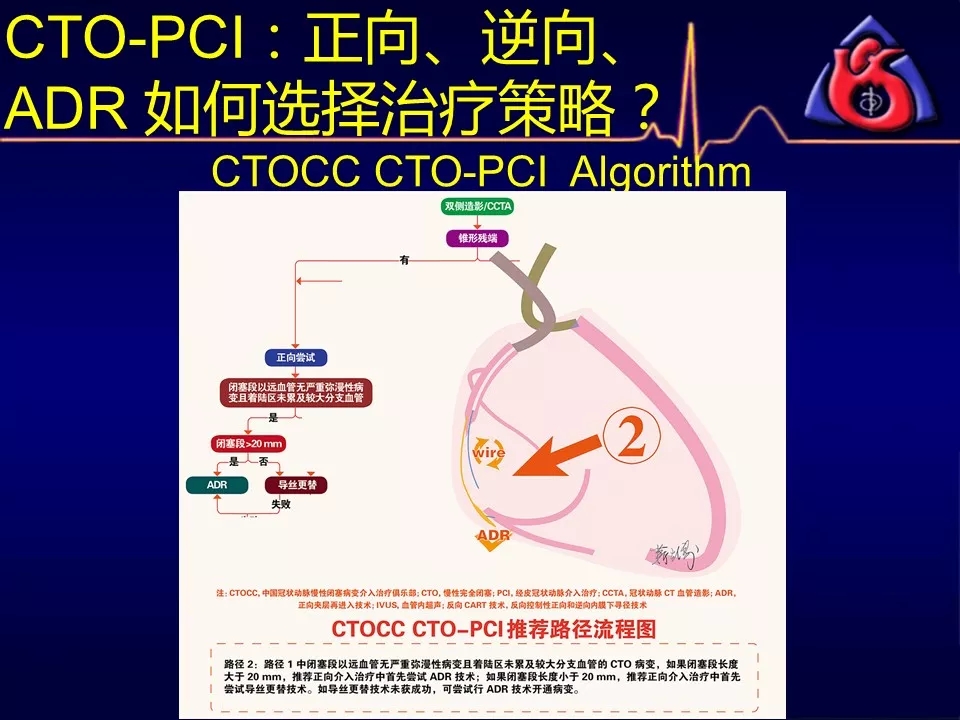

学习CTOCC CTO-PCI流程图的你

如何选择正向、逆向、IVUS指引及ADR技术?

《CTOCC CTO-PCI流程图精讲》